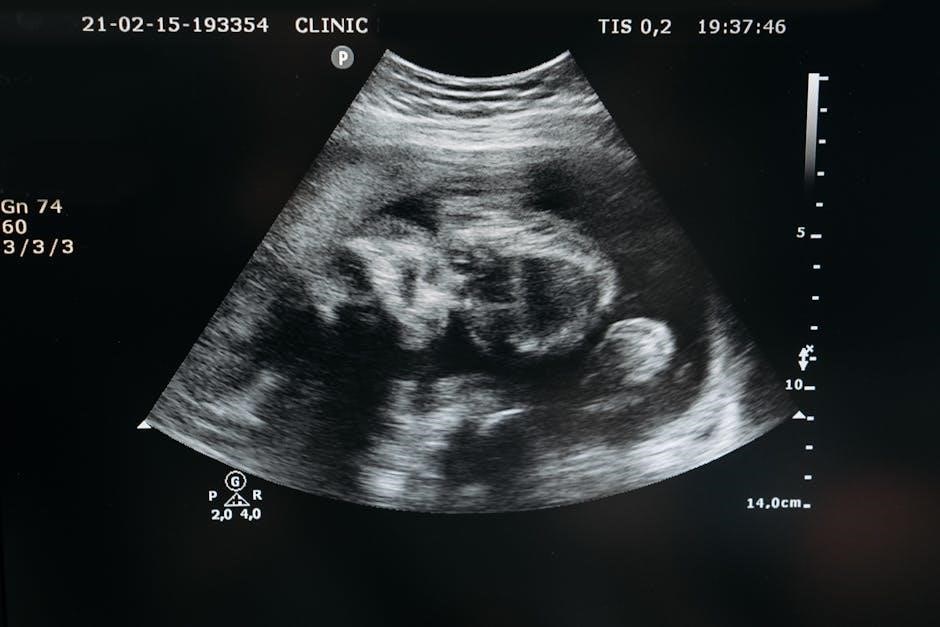

Ultrasound guidance in BBL utilizes high-frequency sound waves to create real-time images of the patient’s anatomy. A transducer, the handheld device, emits these waves which penetrate the skin and bounce back when they encounter different tissue densities.

These echoes are then processed by a machine, translating them into a visual representation on a screen. This allows the surgeon to clearly differentiate between subcutaneous fat, muscle, and blood vessels before and during the fat injection process.

Essentially, it’s like having a live X-ray, but without the radiation exposure. The surgeon can precisely visualize the depth and location of the injections, ensuring the fat is deposited safely above the muscle layer.

This is critical because injecting into the muscle significantly increases the risk of fat embolism – a potentially fatal complication. Ultrasound provides a dynamic view, allowing for adjustments during the procedure to optimize fat placement and maximize safety.

Ultrasound excels at delineating the distinct layers beneath the skin, particularly the subcutaneous fat. This layer, situated between the skin and the muscle, is the ideal target for fat grafting during a BBL procedure. The ultrasound image displays the subcutaneous fat as a relatively homogenous, echogenic (bright) area.

Surgeons can assess the thickness and quality of this fat layer, identifying optimal injection points. The technology also reveals the superficial fascial system (SFS), a network of connective tissue within the subcutaneous fat, which can guide cannula placement for even distribution.

Crucially, ultrasound clearly distinguishes the hypoechoic (darker) muscle layer beneath the fat. This visual separation is paramount, as it allows the surgeon to confirm they are consistently injecting above the muscle, avoiding the dangerous intramuscular placement.

The most significant risk associated with BBLs is fat embolism, often stemming from unintentional injection into the gluteal muscle. Ultrasound guidance directly addresses this danger by providing real-time visualization of the muscle layer. Surgeons can continuously monitor the cannula’s position, ensuring it remains entirely within the subcutaneous fat.

Without ultrasound, surgeons rely on tactile feel, which can be unreliable, especially in patients with varying body compositions. Ultrasound eliminates ambiguity, offering a clear visual confirmation of safe injection depth.

Any deviation towards the muscle is immediately apparent on the ultrasound screen, prompting the surgeon to adjust the cannula’s trajectory. This proactive approach drastically reduces the likelihood of intramuscular injection and subsequent complications.